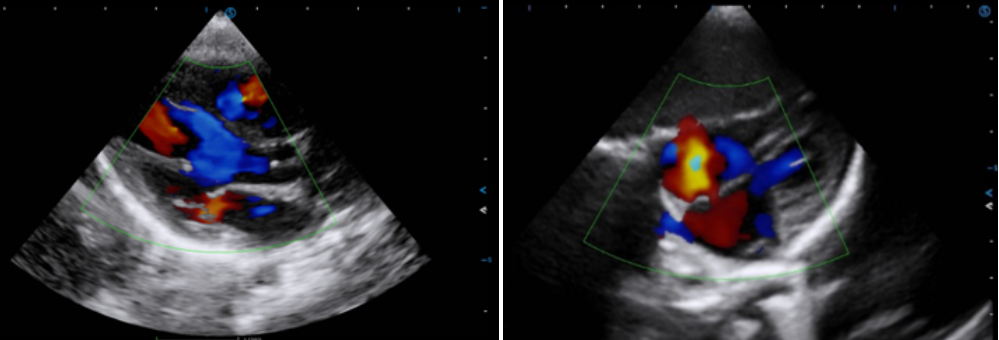

· Auto SG automatically traces and evaluates global and segmental myocardial motion, providing quantitative results for LV GLS and WMSI in a bull’s-eye diagram and curves for assessment.